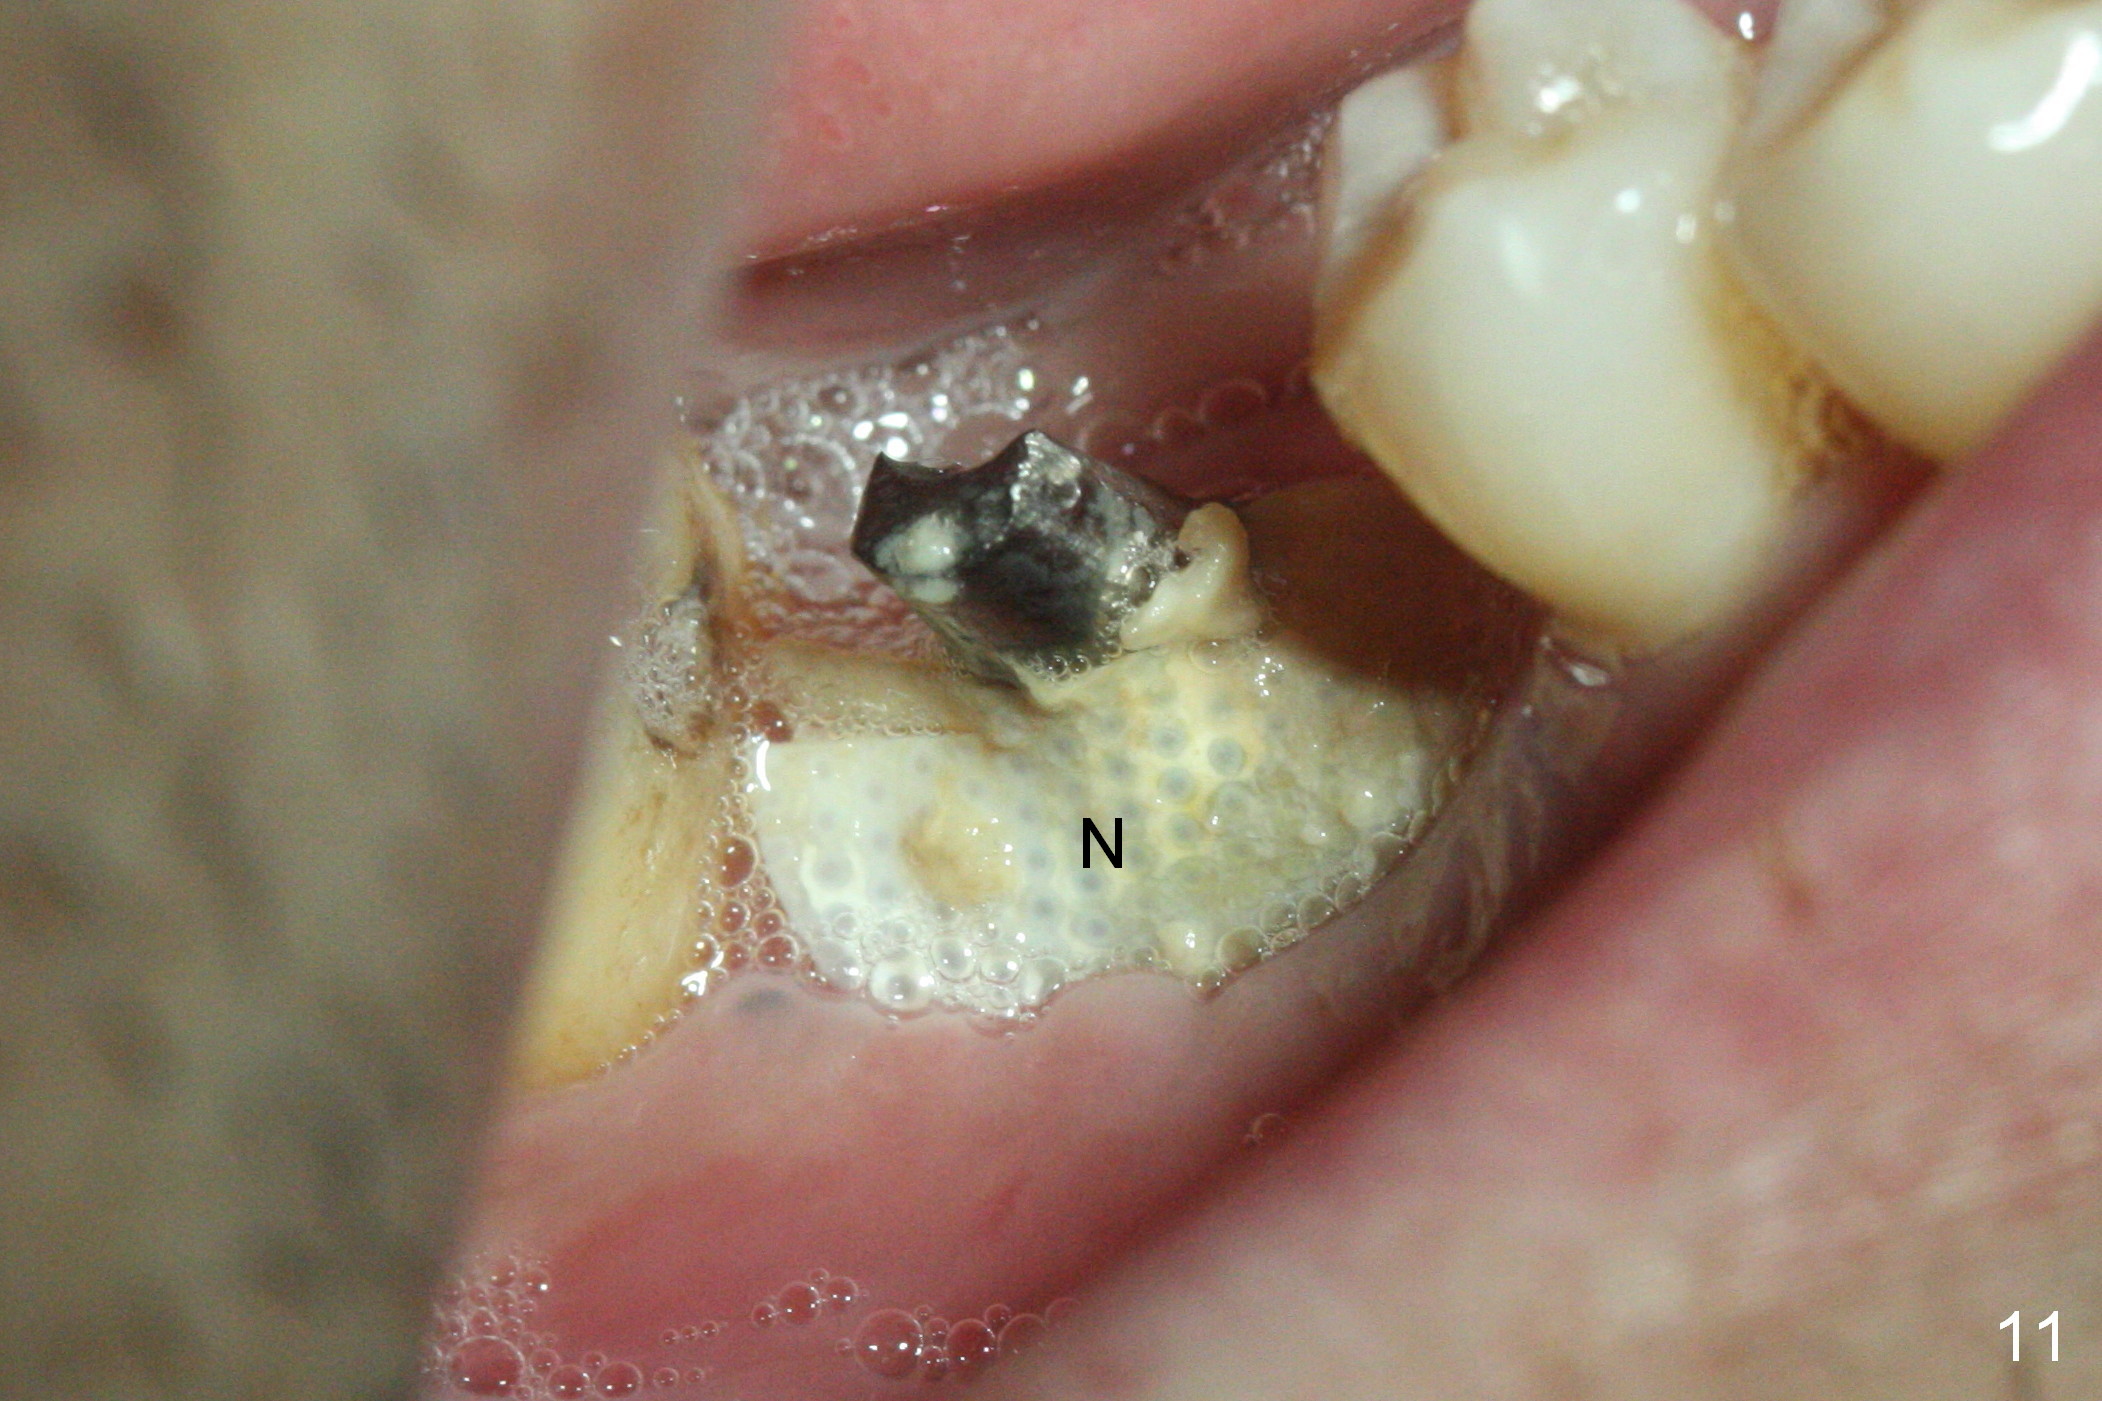

The non-resorbable membrane stays in place 1 month postop (Fig.11 N). When it is removed, the buccal aspect of the cuff of the angled abutment is not covered by bone graft or granulation tissue (Fig.12 C). In fact, the membrane does not hold the bone graft in place as effectively as a provisional. The space is filled with a piece of gauze (Fig.13) while the abutment is reduced for provisional and MO composite at #31 is placed. Before seating the provisional (Fig.14 P), a piece of collagen plug is inserted into the space (*) after removal of the gauze.